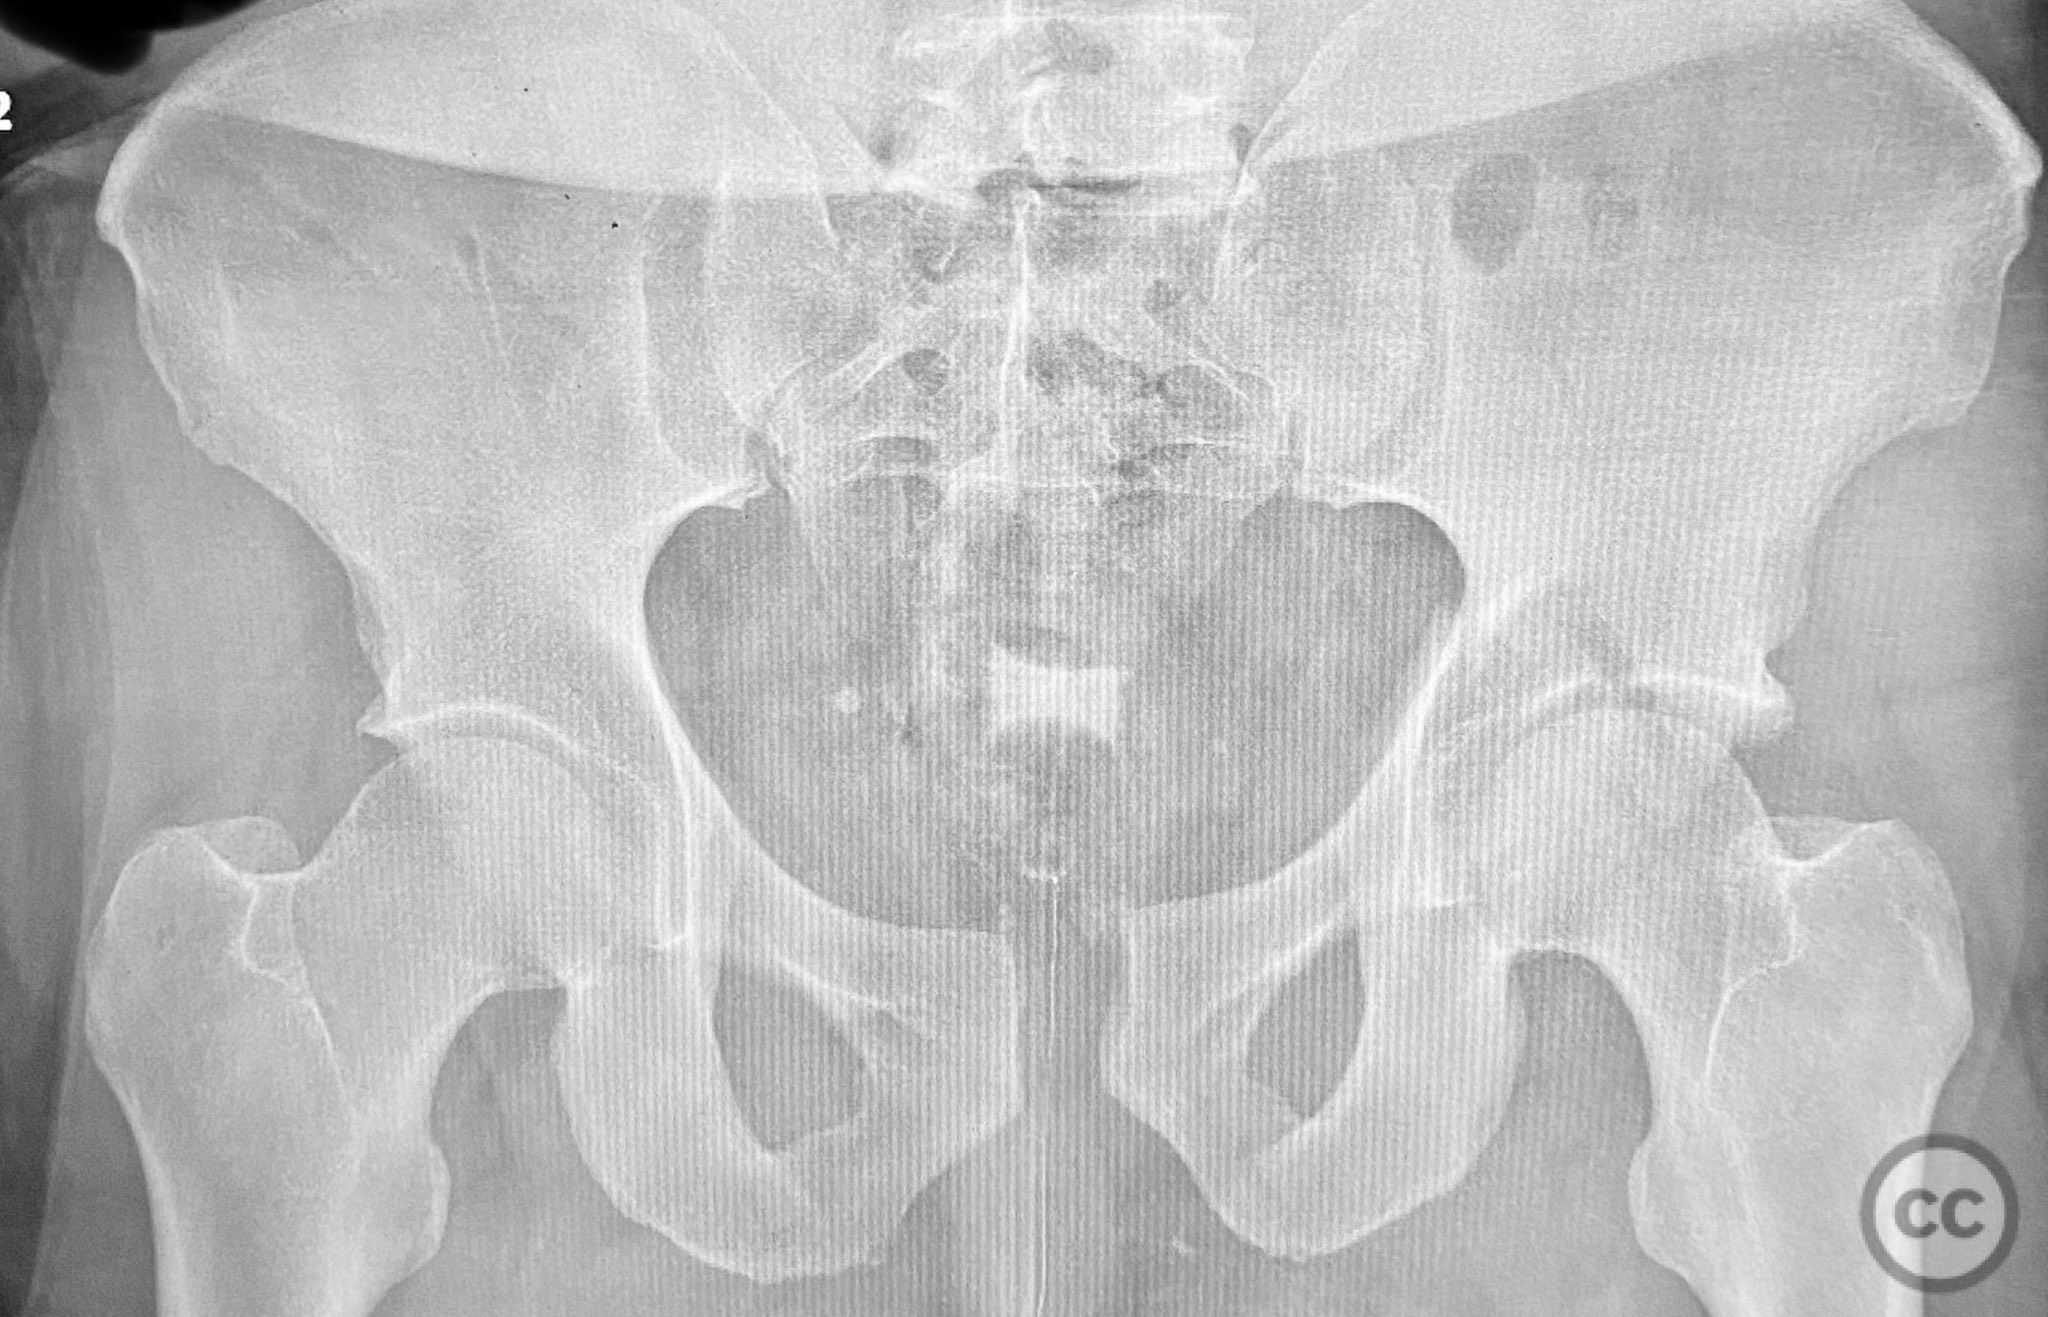

Clinical and radiological findings:  Adult male with a closed, comminuted left femoral shaft fracture and complex pelvic ring injury. Initial imaging demonstrated bilateral sacroiliac (SI) joint disruptions and a left-sided transtectal transverse acetabular fracture (Letournel-Judet: transverse type), with the fracture line exiting through the posterior wall region but without a discrete posterior wall fragment. The femoral head was displaced caudally, following the unstable distal acetabular segment, resulting in loss of congruency with the intact acetabular dome. There was also a symphyseal disruption. No associated abdominal, visceral, thoracic, cranial, or other injuries were present. Application of a circumferential pelvic binder resulted in visible changes in pelvic alignment on imaging. AO/OTA Classification: - Pelvic ring: 61-C1.3 (bilateral SI joint disruption, complete instability) - Acetabulum: 62-B1 (transverse fracture) - Femur: 32-C3 (comminuted diaphyseal fracture)

Planning remarks:  The preoperative plan involved staged management: initial resuscitation and provisional stabilization with a circumferential pelvic binder, followed by operative reduction and fixation of the pelvic ring using an anterior two-pin external fixator for SI joint compression and reduction, percutaneous iliosacral (IS) and transsacral (TS) screw fixation, and subsequent intramedullary nailing of the femur. Definitive acetabular fixation was planned via a posterior Kocher-Langenbeck approach in the prone position.